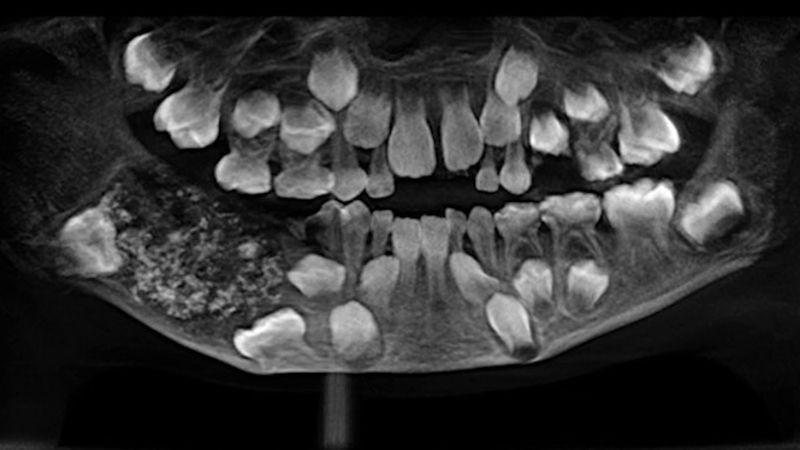

Hindistan’ın Chennai kentinde bir çocuk üç yaşından beri sağ alt çenesinde ağrılı bir şişlik yaşıyan ve bütün tedaviyi reddediyordu. Dört yıl sonra, çocuğun ebeveynleri röntgen ve tomografi çektirmek için Chennai şehrindeki Saveetha Diş Koleji ve Hastanesine geldi. Yapılan taramalar sonunda ufak çocuğun ağzında yüzlerce irili ufaklı yüzlerce diş olduğu görüldü.

7 yaşındaki çocuğunun, ‘Kompleks ve Kompaund Odontoma’ adında ender bir diş hastalığı olduğu ortaya çıktı. Çocuğun sağ alt çene bölgesinin röntgenini ve BT taramasını çeken doktorlar, diş yapısını incelediğinde şoke oldu. Çocuğun ağzında fazladan 500’den fazla diş olduğu anlaşıldı.

Ağız Diş Çene Hastalıkları ve Cerrahisi Anabilim Dalı Profesörü P. Senthilnathan yaptığı açıklamada, "Genel anestezi uyguladıktan sonra çeneyi açtık ve içinde bir kese gördük. Yaklaşık 200 gram ağırlığındaki kese, dikkatlice çıkarıldı ve kesenin içinde 526 küçük, orta ve büyük boy diş bulundu" dedi.